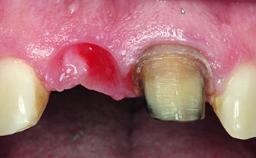

A healthy 37-year-old female patient was referred for a consultation on the replacement of missing tooth 21 with an implant-supported restoration. She stated that several years previously the tooth had been traumatically avulsed following a motor vehicle accident. The tooth was replaced with a three-unit fixed partial denture (FPD) immediately afterwards. Over time, she became disillusioned with the FPD and looked for a different option, including orthodontic therapy. She presented still in her orthodontic appliances, with the pontic sectioned free from the FPD but attached to the archwire. Her orthodontist felt that orthodontic treatment had been successfully completed, but nevertheless referred her before removing the appliances in case adjustments were necessary.

Bone Volume Deficient horizontally, allowing simultaneous augumentation